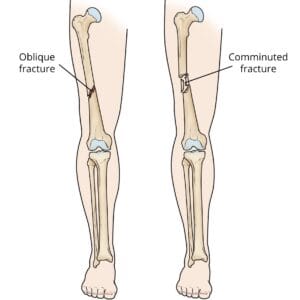

Hip Patient informationA hip fracture refers to a break in the upper segment of the femur, commonly known as the thighbone. These fractures are most frequently seen in older adults with weakened bones due to osteoporosis. However, in younger individuals, hip fractures typically result from high-impact incidents, such as falling from a